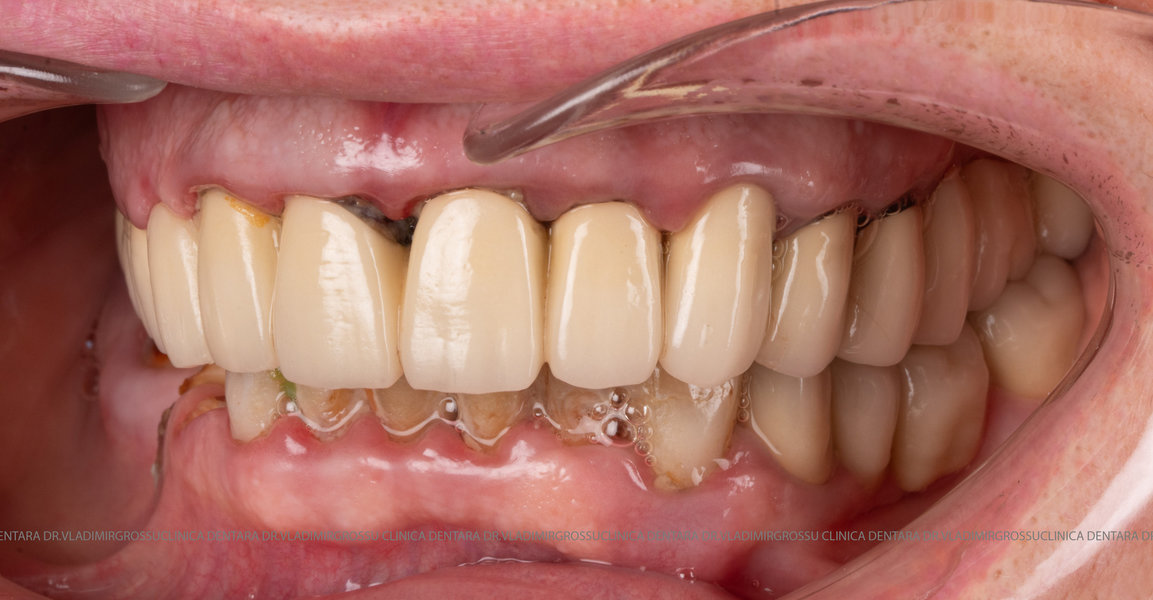

- Prima etapă constă în inserarea implanturilor și fixarea unei proteze provizorii, realizate de obicei din masă plastică frezată, ce este montată în a doua sau a treia zi postoperator. Suturile sunt îndepărtate după 5-7 zile.

Caz 1